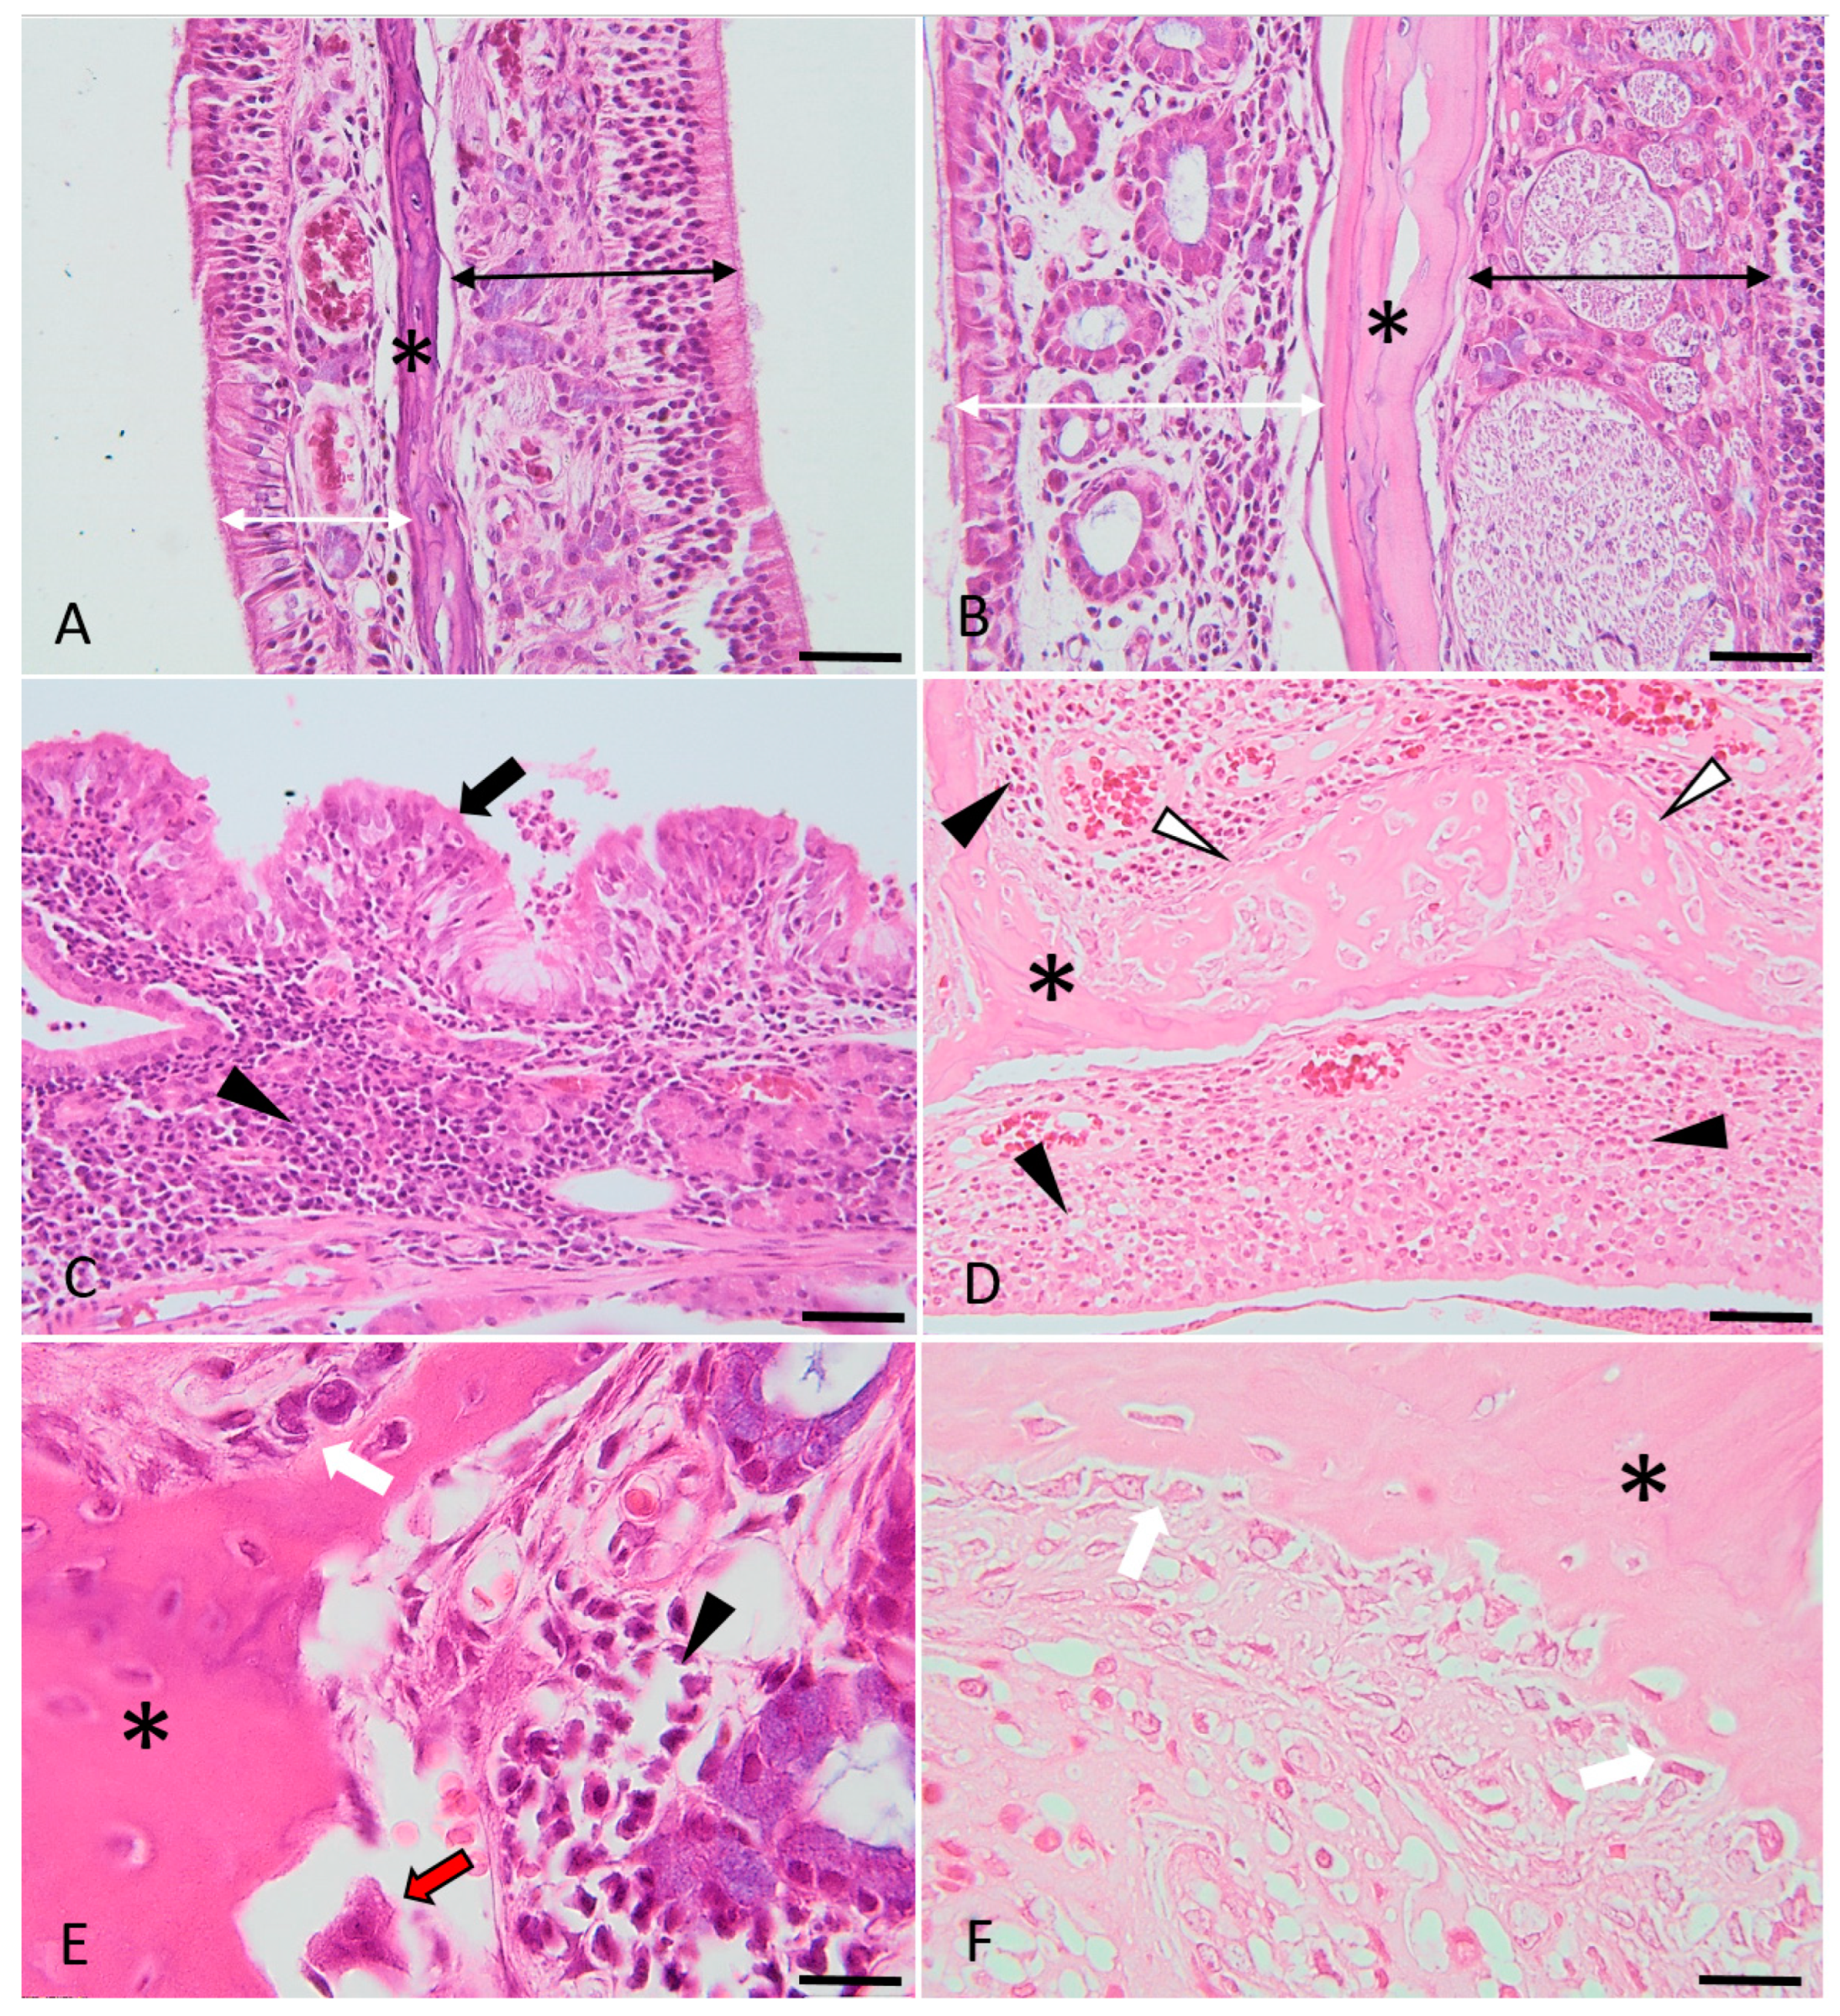

Figure 5.

Histological micrographs presenting the key features of bone changes observed in experimentally induced chronic rhinosinusitis (images (C–F)), compared with the control (images (A,B)). Images (A,B): control images of the nasal turbinates, presenting the respiratory (indicated by the double white arrowheads) and sensory mucosa (indicated by the double black arrowheads) and the trabecular bone (asterisk). Images (C,D): Diffusely, the lamina propria is infiltrated by lymphocytes, plasma cells and macrophages (indicated by the black arrowheads). The respiratory epithelium is multifocally hyperplastic (indicated by the black arrows) or ulcerated (image (D)) and covered by a purulent catarrh. Within the trabecular bone of the nasal turbinates (indicated by the asterisks) (images (D–F)), there is periosteal proliferation with prominent osteoblastic activation and proliferation (images (E,F), white arrows), occasional osteoclastic bone resorption (image (E), red arrow) and multifocal, prominent osteoid deposition (woven and trabecular bone, with variable degrees of mineralization) (image (D), white arrowheads). H&E stain, ob × 20 (images A barr = 100 µm), ob × 40 (images (B–D), scale barr = 50 µm) and ×100 (images (E,F), scale barr = 20 µm).